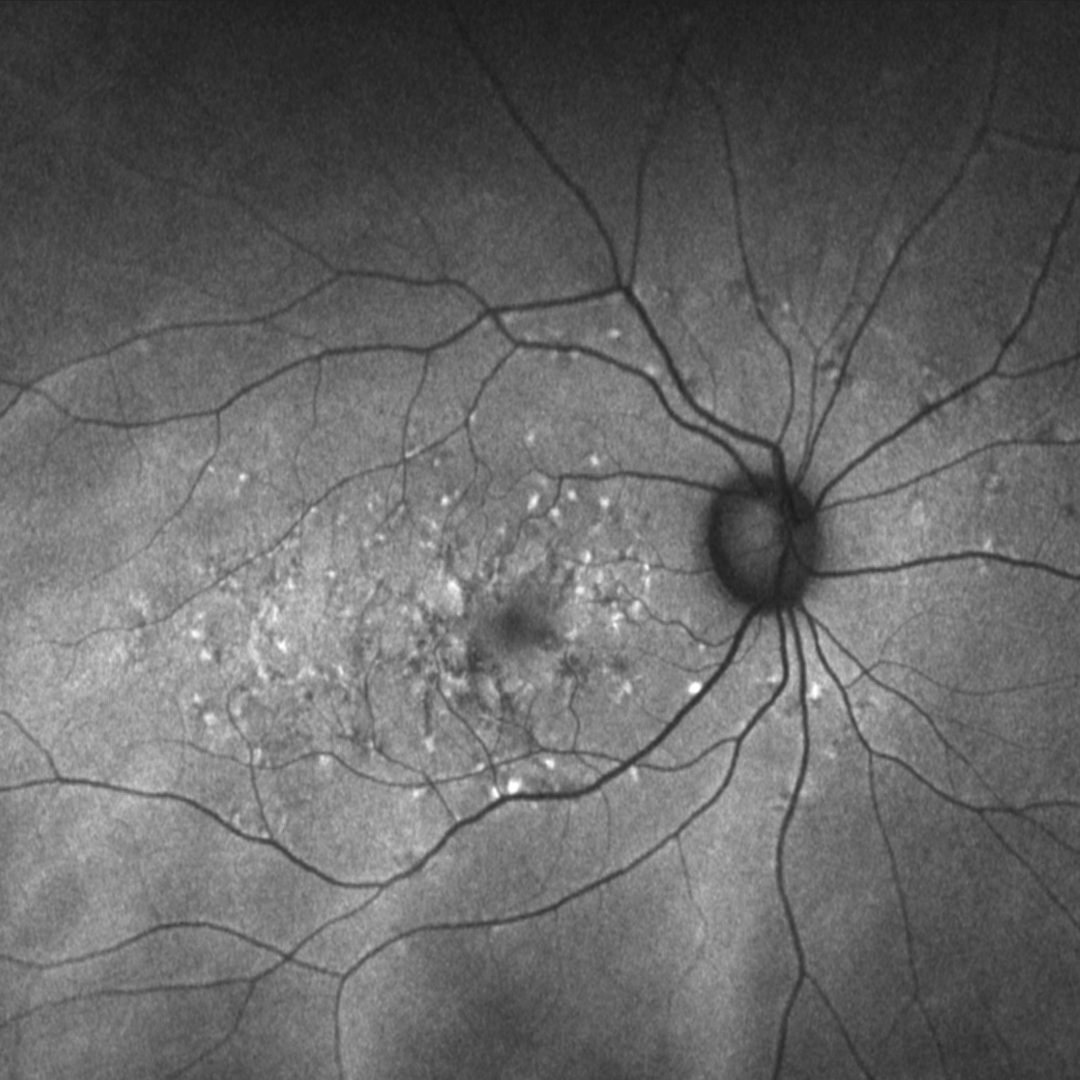

A 57-year-old Middle Eastern female with best-corrected acuities of 6/6+ (20/20+) in each eye.

Fundus photograph and red free image (right eye)